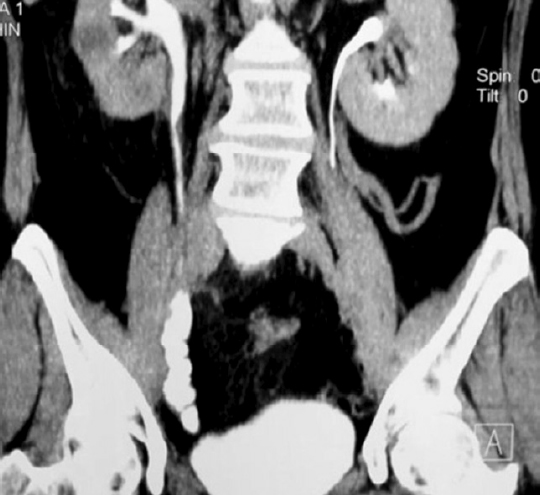

Fig. 10. Bilateral isoperistaltic 7-shaped ileoureteroplasty

Fig. 11. Multisection computed tomography (MSCT) with contrasts of the patient 5 years after bilateral isoperistaltic 7-shaped ileoureteroplasty